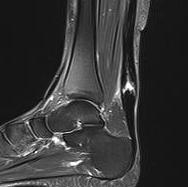

MRI

Indication

- incomplete rupture / clinical uncertainty

- chronic tears - measurement of gap for reconstruction planning

Acute

High grade partial thickness

Chronic retracted